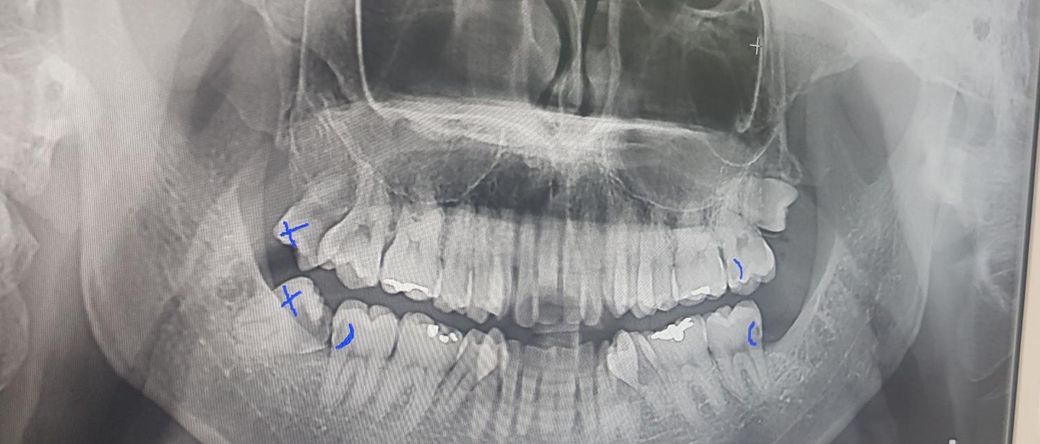

왼쪽 맨 아래 어금니 충치가 신경과 거리가 좀 되는 편인가요?

왼쪽을 할 차례인데 현재 신경과 거리가 좀 먼 편인가요?

그냥 레진으로 끝날 수 있는 상황인가요?

사진으로 봤을 경우에는 왼쪽 아래 어금니의 경우에는 레진으로 충전을 하기에는 잇몸 아래쪽으로 너무 내려간것으로 보입니다. 충치는 사진상으로는 깊어 보이지 않지만 실제적으로 제거했을 경우에 깊을수도 있습니다

1. 일단 레진 또는 인레이로 시도해보되 신경치료 가능성도 있는 상황이라고 보시면 됩니다.

2. 엑스레이 사진보다는 충치의 경우 더 깊은 경향이 많고, 충치 제거하다보면 비 의도적으로 신경이 뚫리기도 합니다.